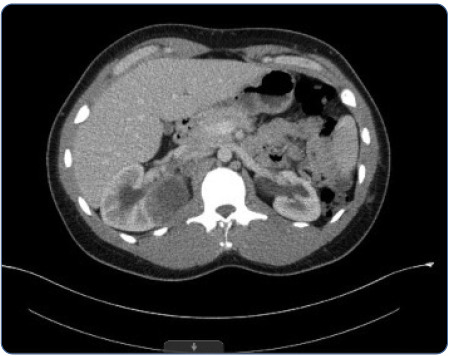

Medullary renal cell carcinomas are exceedingly rare and essentially uniformly and rapidly fatal. Expeditious diagnosis is crucial. Immediate treatment with a clinical trial or platinum-based chemotherapy is needed for metastatic disease given the aggressive nature of medullary renal cell carcinomas. In this article, we discuss a 24-year-old man with no known significant past medical history who presented with a progressive cough and shortness of breath. After evaluation at an urgent care and four evaluations in the emergency department, the patient was admitted and ultimately diagnosed with metastatic medullary renal cell carcinoma. This case highlights the characteristics, presentation, rarity, and aggressiveness of medullary renal cell carcinoma.